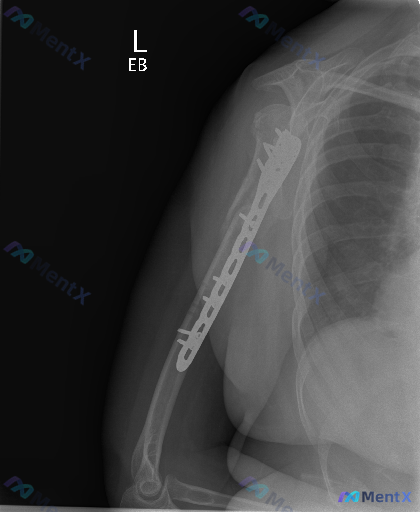

左肱骨骨折内固定术后复查X光,这张片子的「异常」重点该怎么看?

整理到一份左肱骨骨折内固定术后的正位X光片资料,大家可以一起看看:

- 患者是左侧肱骨骨折术后复查,影像显示左侧肱骨近端至中段有解剖锁定钢板及多枚螺钉固定,钢板沿肱骨外侧放置,与骨皮质贴合紧密,未见明显钢板断裂、螺钉松动退出。

- 肱骨干可见陈旧性骨折痕迹,骨折线已模糊,断端周围有连续性骨痂形成;肱骨近端(大结节/外科颈区域)有陈旧性骨折后的骨形态改变与结构重塑。

- 肩关节对位基本正常,关节间隙未见明显狭窄;可见部分肱骨远端,小头与滑车形态尚可,未见明显脱位半脱位。

- 肱骨干远端骨皮质密度和厚度基本正常;肱骨近端因内固定遮挡与术后重塑,局部骨密度不均匀。

- 上臂软组织轮廓清晰,未见明显异常肿胀或透亮气体影;除手术内固定物外,未见其他异常高密度异物。

不过同时有提示说「这张图像存在异常」。单看目前这些信息,再结合「存在异常」的背景,你觉得这个病例的异常重点该往哪个方向考虑?